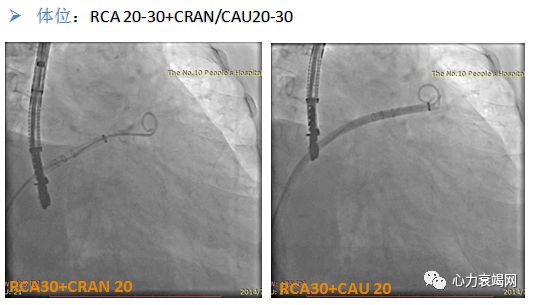

左心耳造影 (RAO20-30+CRAN20/CAU20),测量最大开口直径